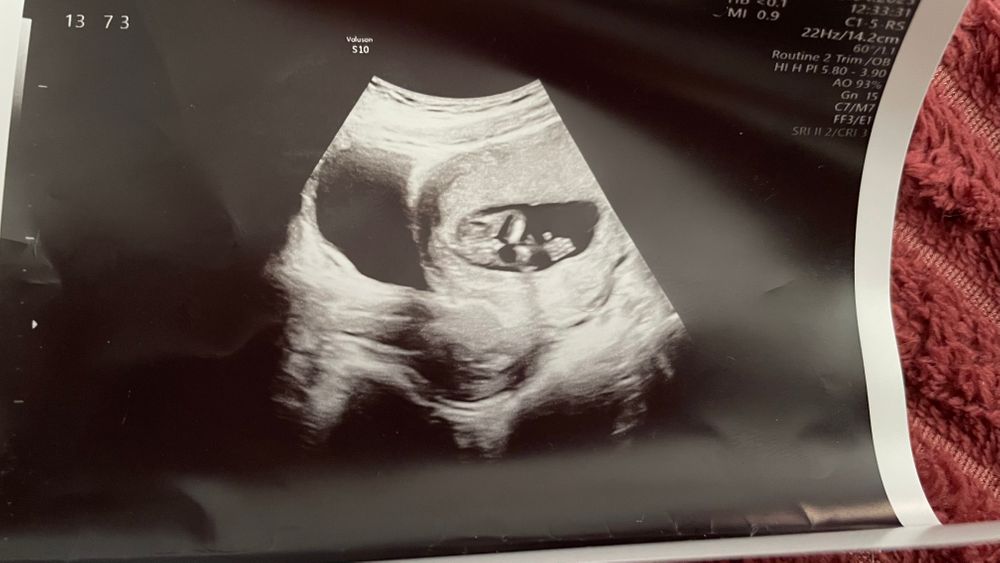

Диана в Благополучная беременность 3 года Девочка или мальчик? Пол малыша Девочки, как думаете кто? Посмотрите еще 20 записей на эту тему Отменить Ответить Стеша сколько недель на фото? 08.06.2023 Ответить Стеша мальчик 08.06.2023 Ответить Olya19 На мальчика похоже,если я правильно смотрю 25.04.2023 Ответить Юлия Авилова Торчит, как у мальчика 😅 25.04.2023 Ответить Лисица Мальчик! Узист что сказал? 25.04.2023 Ответить Диана Лиза, на этом узи с фото, сказала мальчик. Пришла через неделю , девочка. Но как после такого фото сказать что девочка не знаю 25.04.2023 Ответить Лисица Диана, очень странно! А на втором УЗИ фото не сделали? 25.04.2023 Ответить Диана Лиза, нет. Не было смысла. Сказала то что не поворачивается в нужную позу и нет смысла фоткать 25.04.2023 Ответить Тишка На мальчика похоже 25.04.2023 Ответить Таро Расклады на зачатие Если я все правильно поняла, то кажется мальчик 25.04.2023 Ответить Тянет на сладкое - признак девочки? Ну вот мы и узнали кто живет у меня в животике 🥰 Чаты Беременных Выберите чат: Январята-2026 Февралята-2026 Мартята-2026 Апрелята-2026 Майчата-2026 Июнята-2026 Июлята-2026 Августята-2026